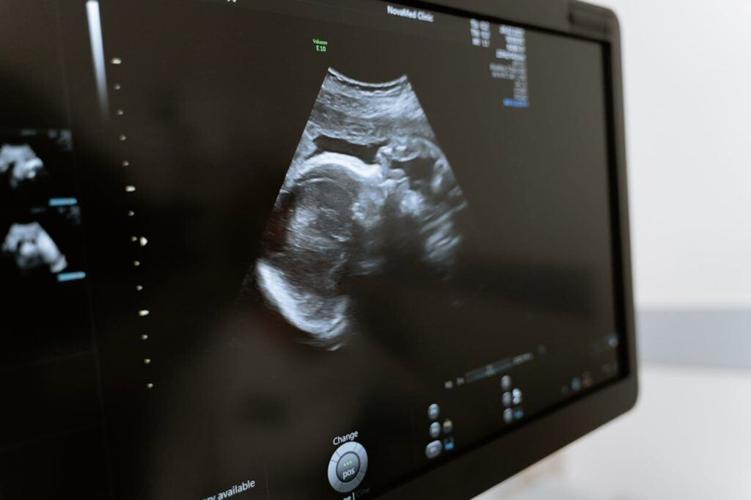

Photo by MART PRODUCTION via Pexels